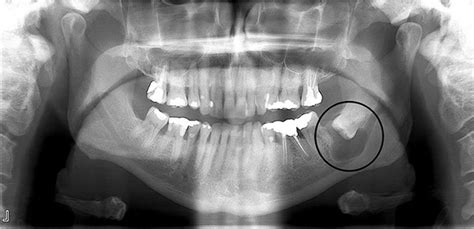

En muchos casos, un quiste dental no produce síntomas al inicio. Puede estar ahí, debajo de la encía, sin que tú lo notes. De hecho, es común descubrirlo de forma accidental en una radiografía de rutina. Cuando un quiste es pequeño y no está infectado, típicamente no duele ni inflama. A medida que aumenta de tamaño, puede empezar a causar presión en el hueso y en los dientes vecinos. A veces notarás un bultito indoloro en la encía o una sensación extraña. Cada caso es distinto, pero incluso sin síntomas evidentes, un quiste no tratado puede seguir creciendo silenciosamente, “comiéndose” el hueso alrededor. Por eso, no debemos ignorarlo aunque no duela.

- Dentígero: Este quiste se produce alrededor de dientes no erupcionados como muelas del juicio que aún no han salido y provoca la pérdida ósea a su alrededor. El quiste dentígero alrededor de una muela del juicio, por lo general debe ser eliminado junto con una extracción de muela del juicio. Esta lesión quística rodea la corona de un diente no erupcionado en posición interósea. Representa casi el 17% de los quistes maxilares y predomina principalmente entre los varones de entre 20 y 30 años de edad, siendo su localización más habitual en los terceros molares maxilares y los segundos premolares mandibulares, seguidos de los caninos, los terceros molares maxilares y los segundos premolares mandibulares. Cuando una muela del juicio está afectada, por lo general, se formará al menos un quiste de este tipo cerca de ella. Se desarrollan en el folículo dental y a menudo pasan inadvertidos debido a que no causan ningún dolor, aunque pueden forzar a los terceros molares a salirse de su posición natural.

- Periapical: Este tipo de quiste se produce alrededor de la punta (ápice) de la raíz de un diente, por lo general como resultado de la infección dentro de ese diente. En general se trata de “quistes” inflamatorios (granulomas) como consecuencia de caries o golpes que provocan la infección del interior del diente (nervio y vasos) y su posterior llegada al hueso debajo de la raíz. Se localiza con mayor frecuencia en la zona anterior de la mandíbula y, en la mayoría de los casos, es completamente asintomático. Los quistes periapicales están causados por la necrosis de la pulpa dental. También llamado quiste radicular es sin duda el quiste más común en los dientes. Los quistes periapicales suelen desarrollarse como resultado de una serie de enfermedades infecciosas que afectan a los tejidos internos del diente. Se trata del quiste dental que se forma en la punta de la raíz del diente. Es el segundo tipo de quiste dental más común tras el radicular, y suele darse en los molares, concretamente en el tercer molar de la mandíbula inferior. En ambos casos el diente infectado debe tratarse con una endodoncia (tratamiento de nervio), re endodoncia o una extracción. Solo en caso de que pasados 6 meses o 1 año no se reduzca la mancha oscura en las radiografías, quizás haya que hacer una cirugía para quitar el quiste y mantener el diente si es posible. Estos son bastante incómodos, ya que son causados por algún tipo de infección en el área de la pulpa dental. El fluido creado por la infección se escapará a través de una pequeña abertura en la parte inferior del diente y quedará atrapado por el tejido circundante; formando un quiste lleno de líquido.